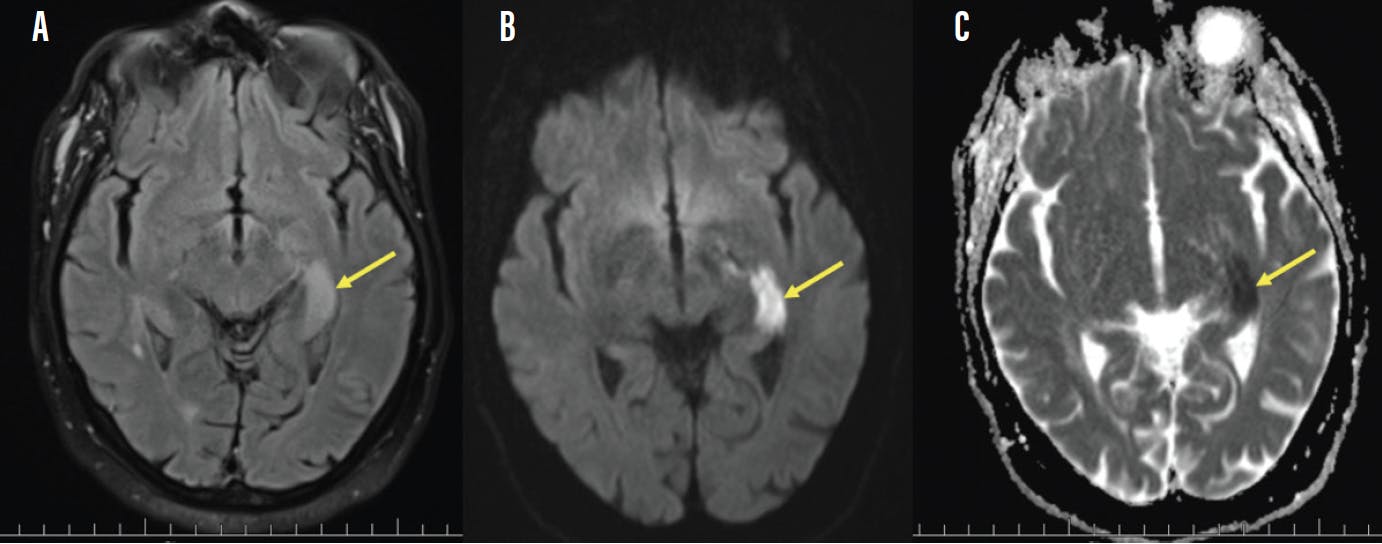

The patient’s BCVA was 20/40 OD and 20/50 OS. His pupils were equal, round, and reactive to light, but with an obvious afferent pupillary defect OS. Extraocular motilities were normal. Automated perimetry confirmed severely restricted confrontational visual fields OU (Figure 1). External examination was normal OU, except for moderate cataract OD and previous cataract surgery OS. Goldman applanation tonometry was 24 mm Hg OD and 34 mm Hg OS. Gonioscopy was normal OU, without angle recession. Dilated fundus examination revealed extensive glaucomatous cupping OU (OS > OD) and severe optic nerve pallor OS (Figure 2). MRI revealed an ischemic lesion involving the anterior left optic radiations (Figure 3), thus explaining the patient’s new visual complaint secondary to stroke.

The chronologic timeline of the patient’s visual field defects was relatively complicated. The patient’s complaints initially started with mild inferior nasal visual field defects OU, consistent with his glaucoma diagnosis 5 years prior. This was followed by an acute NAAION OS, which resulted in a commonly associated inferior altitudinal defect, which overlaid the initial nasal glaucomatous visual field defect OS (Figure 4).2 The patient then was lost to follow-up for approximately 5 years, allowing his untreated glaucoma to develop a dense left superior arcuate defect OS. His most recent stroke of the anterior left optic radiations resulted in complete right-sided hemianopias OU, which overlaid all the previously accrued visual field defects (Figure 5).